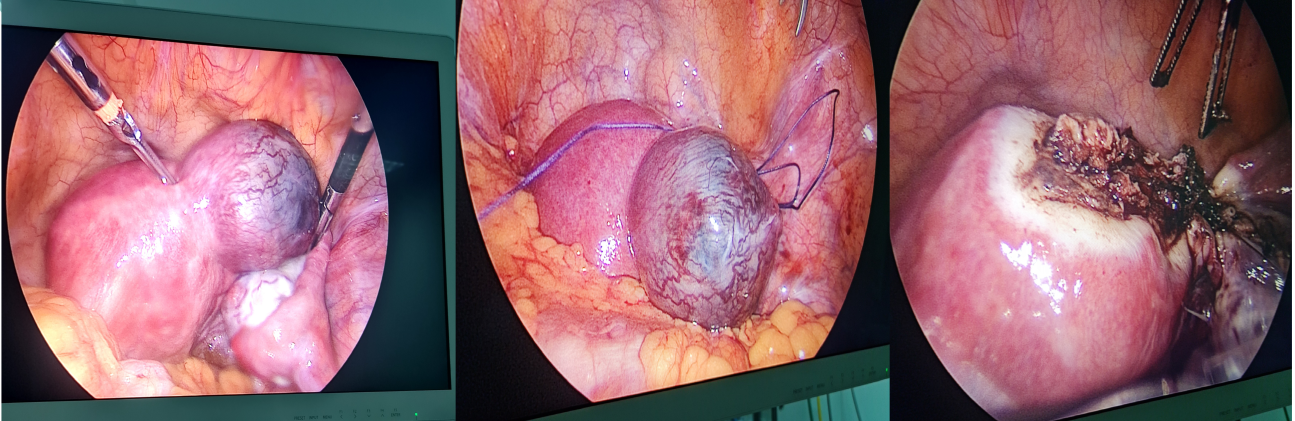

Ca lâm sàng: Bệnh nhân nữ 28 tuổi, PARA (1001), trể kinh hơn 1 tháng, test thai dương tính, vào viện vì đau bụng vùng hạ vị, siêu âm phát hiện thai ngoài tử cung ở đoạn kẽ, tim thai dương tính, thai khoảng 9 tuần, beta hcg 81206 mIU/ml, bệnh nhân được chỉ định và phẫu thuật thành công bằng phương pháp khâu hình túi và cắt góc qua nội soi. Bệnh nhân được xuất viện sau 4 ngày.

Hình 1: Phẫu thuật thai đoạn kẽ tại bệnh viện đa khoa Tỉnh Quảng Trị